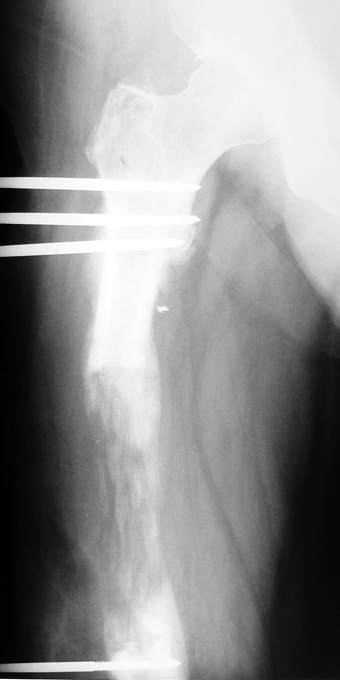

Kronik osteomiyelit, kemik ve yumuşak dokularda nekroza yol açar. Ölü kemik, patojen mikroorganizmalara ev sahipliği yapan bir nidus oluşturur. Konağın savunma sistemleri, mikroorganizmalarla baş etmek için sıklıkla optimal koşullarda değildir. Dolaşım bozukluğu yüzünden enfeksiyon bölgesine antibiyotikler yeterince ulaşamaz. Bu nedenle ölü dokuların ortamdan tamamen uzaklaştırılması gerekir (radikal debridman).

Uygun radikal debridman tüm nekrotik kemik ve yumuşak dokuların çıkartılmasını gerektirir, ve sıklıkla uzuvda instabiliteye neden olur. Kalan kemik ve yumuşak doku defektinin bir şekilde fiksasyonu ve rekonstrüksiyonu gereklidir. İlizarov’un ortaya koyduğu distraksiyon osteogenezi yöntemi, kaynamanın elde edilmesi, deformitenin düzeltilmesi, bacak boy eşitsizliğinin giderilmesi ve segmental defektlerin rekonstrükte edilmesi için başarıyla kullanılmaktadır.

Eksternal fiksatör ile geçen süre (eksternal fiksasyon indeksi), gereken distraksiyon miktarına bağlıdır ve bu süre boyunca bazı komplikasyonlarla karşılaşılabilir. Distraksiyon dönemi sona erdikten sonra, distraksiyon süresinin iki katını aşan konsolidasyon döneminde hastalar eksternal fiksatörü zorlukla tolere edebilirler. Yeterli konsolidasyon sağlanmadan eksternal fiksatör çıkartılırsa ise kırıklar, deformite ve kısalık oluşabilir. Hastanın fiksatör ile birlikte geçirdiği sürenin azaltılması ve böylece hasta konforunun ve aktivite düzeyinin arttırılması için intramedüller çivi üzerinden uzatma yöntemi uygulanmaktadır. Bu yöntemde distraksiyon dönemi sona erdiğinde kemiğin içindeki çivi statik olarak kilitlenmekte ve eksternal fiksatör çıkartılmaktadır. Stabilizasyon intramedüller çivi tarafından sağlandıktan sonra konsolidasyon dönemi gerçekleşmektedir. Bu şekilde hem eksternal fiksatörün uzun süre kalmasından hem de erken çıkartılmasından kaynaklanan komplikasyonların önüne geçilmektedir.